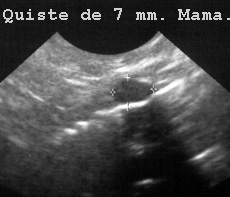

Las lesiones en mama (Fig 72),

72QUISTM.JPG (16711 bytes)

Fig 72